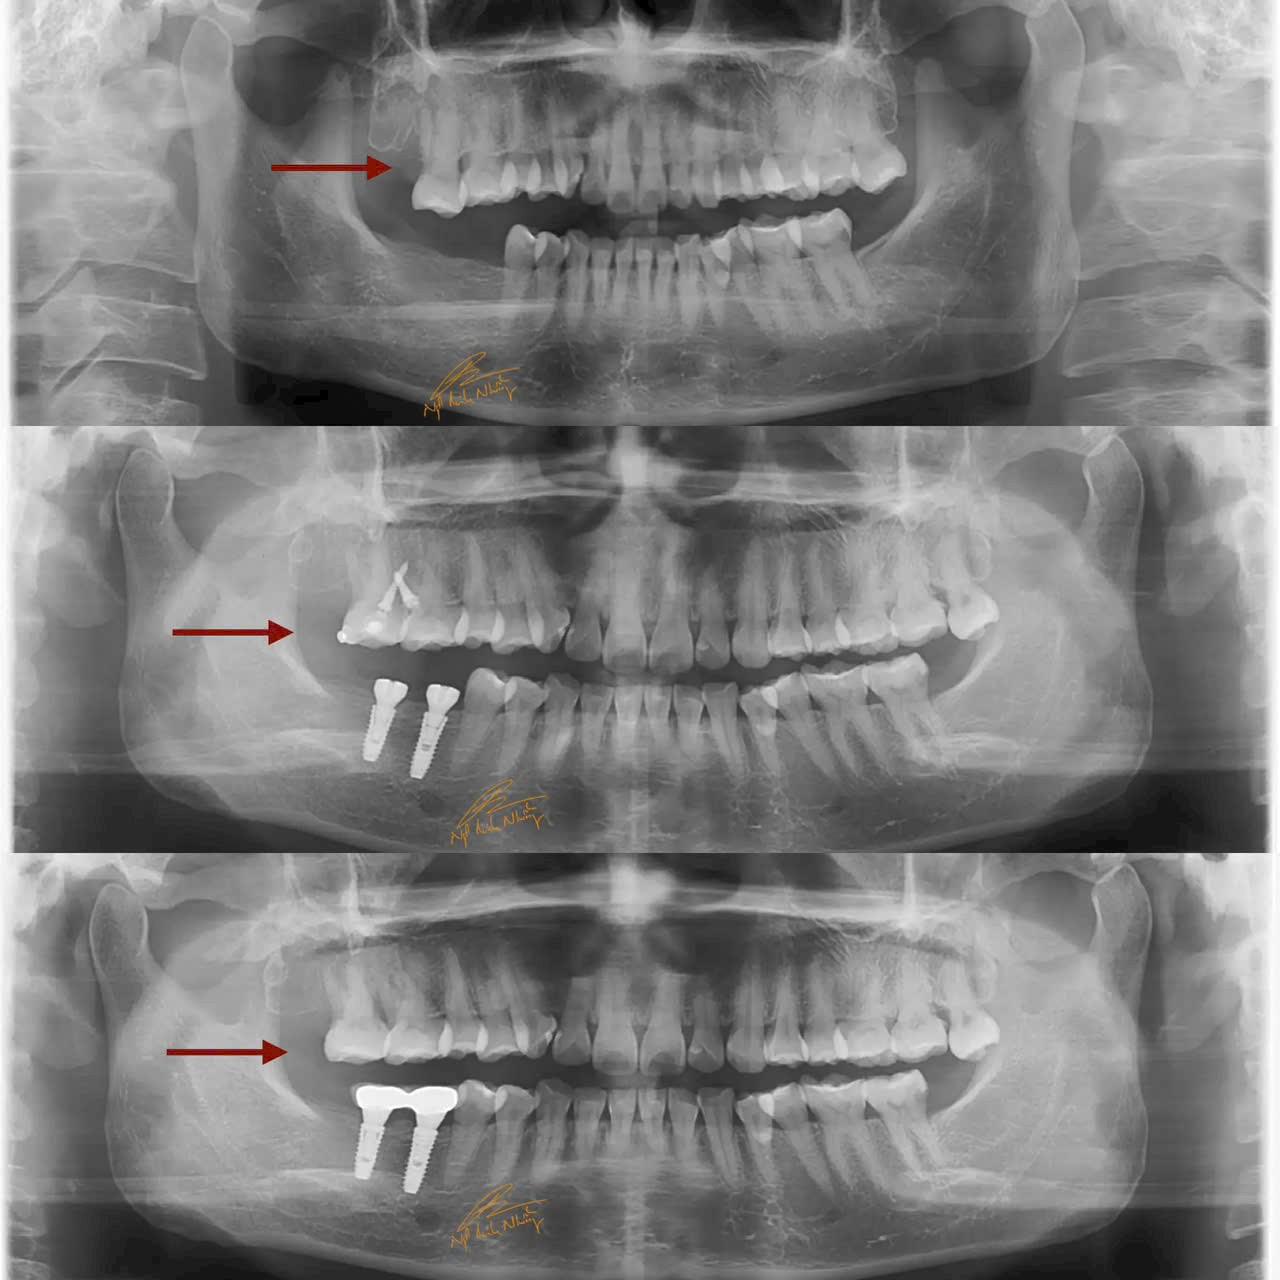

Teo xương hàm : Khi mất răng, xương hàm không còn được kích thích bởi các lực nhai, dẫn đến việc mất dần chất lượng và khối lượng xương tại khu vực mất răng. Điều này có thể làm thay đổi khuôn mặt và làm giảm khả năng lắp răng giả hoặc cấy ghép sau này.

Di chuyển các răng còn lại : Khi mất răng, các răng còn lại có thể bị xô lệch, làm thay đổi cấu trúc của hàm và gây ra các vấn đề về khớp cắn.

Cấy ghép răng (Implant) : Đây là phương pháp phổ biến và hiệu quả nhất để phục hồi răng đã mất. Cấy ghép răng giúp phục hồi chức năng nhai và ngăn ngừa tình trạng teo xương hàm. Cấy ghép được cấy vào xương hàm và có thể lắp răng giả lên đó.

Nếu bạn mất răng lâu ngày, hãy tham khảo ý kiến bác sĩ nha khoa để chọn phương pháp phục hồi phù hợp. Việc phục hồi răng càng sớm càng tốt sẽ giúp hạn chế các tác động tiêu cực đối với xương hàm và các răng còn lại.